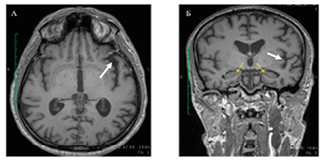

лППА |

Трудности актуализации – подбора и называния слов. Нарушение повторной речи. Сужение объема слухоречевой памяти |

Атрофические изменения в височной и теменной долях доминантного полушария |

|

сППА |

Нарушение номинативной функции речи. Нарушение понимания семантики слов |

Атрофические изменения в области левой височной доли левого полушария |